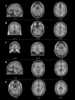

Polycystic osteodysplasia with progressive dementia

Polycystic lipomembranous osteodysplasia with sclerosing leukoencephalopathy is a rare disease characterised by early-onset dementia and multifocal bone cysts. It is also known as Nasu–Hakola disease. [Source: Wikipedia ]